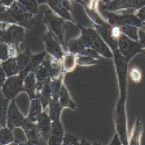

轻柔、次数少,防止细胞形态异常或生长受阻。 HGC-27 细胞 人胃癌细胞,来自于未分化胃癌,能产生并分泌黏液素[7]。 培养条件:RPMI 1640 培养基,10% 胎牛血清,2 mM 谷氨酰胺,10 mM HEPES[8]。 图 3. HGC-27 细胞低密度和高密度生长形态[9]。 注意事项: 1. 定期换液与污染监测:每 2-3 天换液,防止废物堆积或 pH 波动;定期查细胞形态、增殖,排查污染